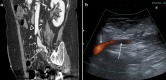

Fig. 14

Abdominal MDCT examination. a The sagittal plane reconstruction shows an enhancement defect (long arrow) in the left common iliac vein (short arrow) due to a thrombus. Abdominal aorta (head arrow). b Power Doppler US shows a thrombus (long arrow) in the left common iliac vein (short arrow)